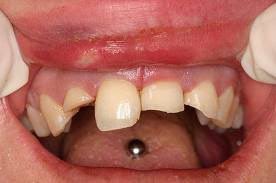

مع انتشار استعمال الحلق في منطقة الشفة واللسان.. أجد من واجبي التحذير من مضارها على المدى البعيد كإنحسار اللثة1️⃣أو تفرق الأسنان4️⃣والمدى القريب كالإلتهابات الحادة2️⃣وكسور الأسنان 3️⃣

فوجود هذه الاجسام المؤذية في مناطق دقيقة وحساسة غير مستحب